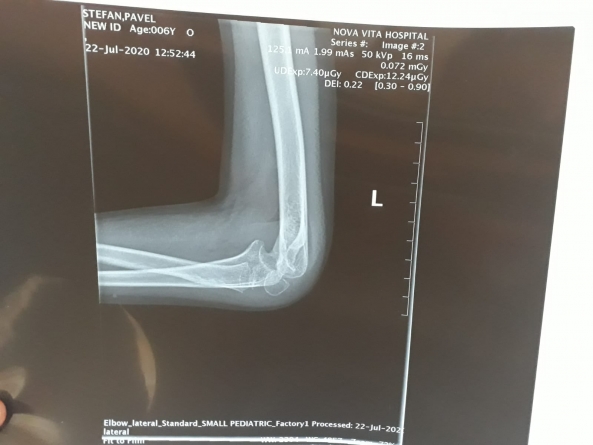

Apel umanitar: Un băiat de șase ani din Ocoliș are nevoie ajutorul nostru! Necesită tratament pentru a-și mișca mâna, iar costurile sunt mari!

Situație dificilă pentru o familie din satul Ocoliș, comuna Groși. Băiatul în vârstă de numai șase ani are nevoie de un tratament costisitor pentru a-și putea folosi din nou mâna. Ajută și tu!

Necazurile au început chiar de Ziua Copilului, în 1 iunie 2019. Atunci, micul Ștefan Pavel se juca, însă, din păcate, a căzut tocmai pe cotul stâng. Din păcate, însă, intervențiile chirurgicale nu l-au putut ajuta pentru a-și folosi din nou mâna (vezi imaginile atașate cu radiografia brațului stâng).

Primăria Groși a publicat un anunț umanitar. “Familia Pavel din localitatea Ocoliș, are nevoie de sprijinul nostru. Pavel Ștefan, un băiat de doar șase ani are nevoie de o operație la mâna stângă pentru a nu rămâne incapabil de a o mai mișca. Băiatul a trecut prin două operații, din care a rezultat o artrofiere a articulațiilor mâinii stângi, fiind incapabil să o îndrepte. Acum au oportunitatea să rezolve această problemă printr-o operație de eliberare a articulației și neuroliza, la Clinica Acibadem, în Turcia, toate costurile ajungând la un total de 12.000 euro, familia și cetățenii din localitatea Ocoliș reușind să strângă o parte din bani”, se arată în apelul publicat.